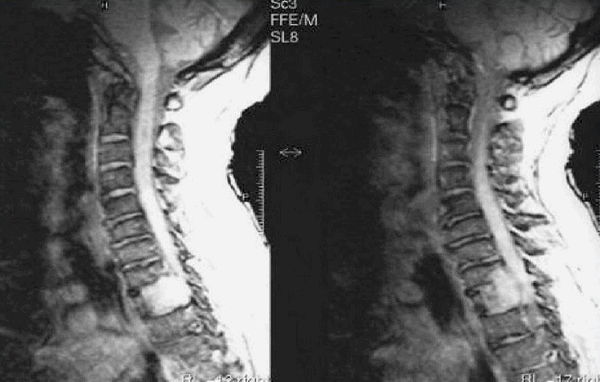

Снимки МРТ мягких тканей шеи

Рисунок 1,2. МРТ мягких тканей шеи (Т2-ВИ и Т1-fs-ВИ контрастное усиление). Патологических образований в структуры щитовидной железы не выявлено.